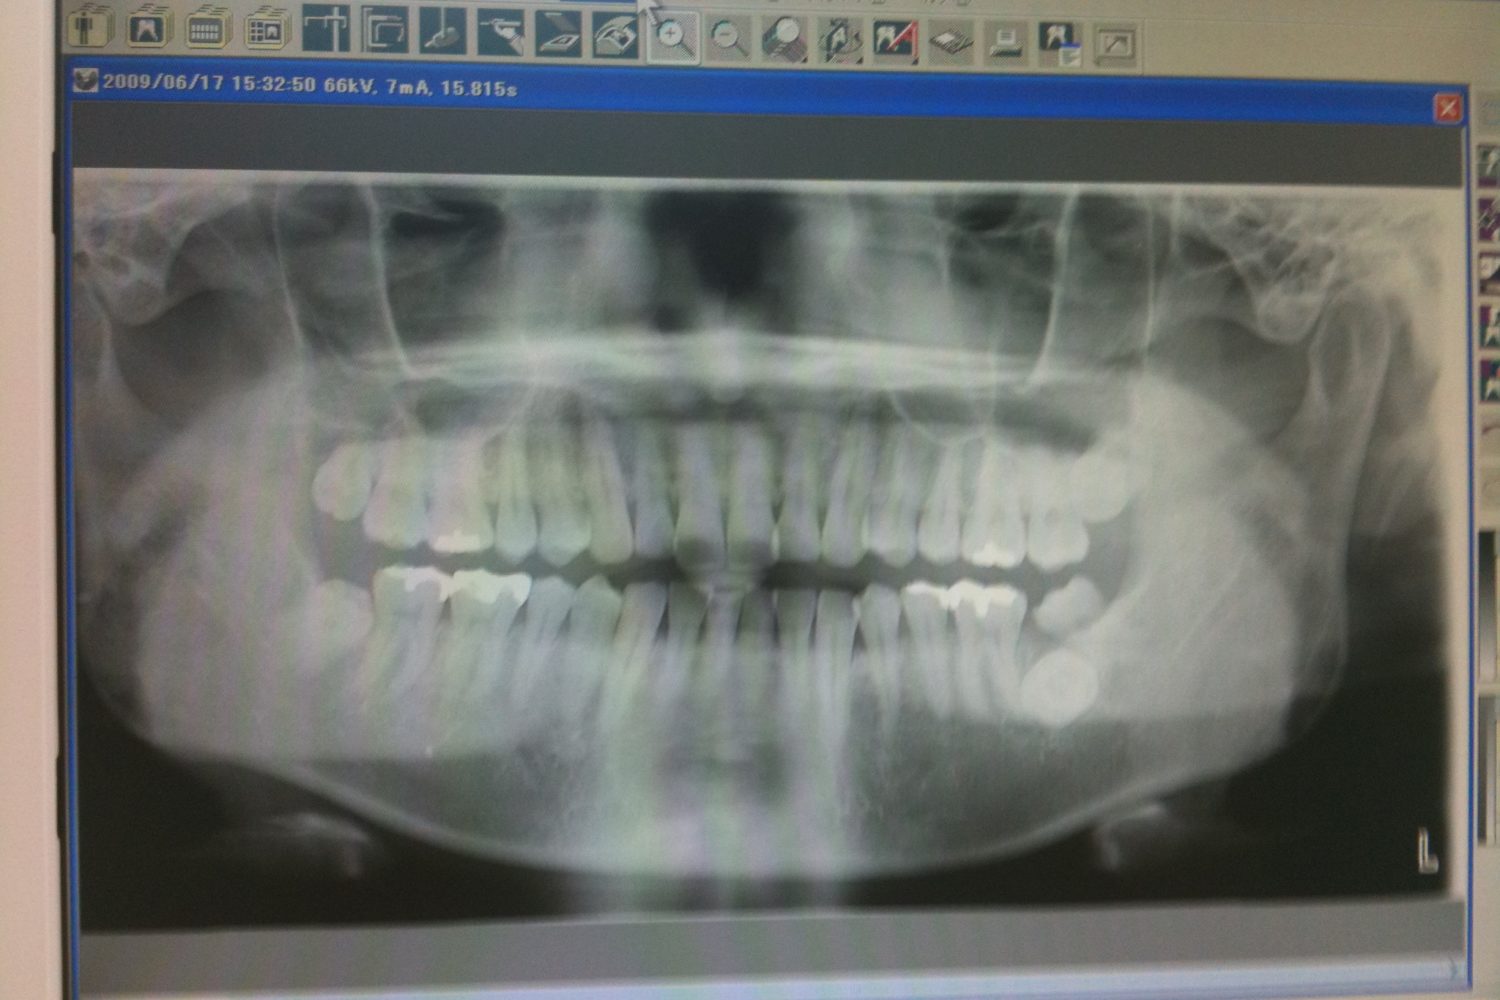

レントゲン